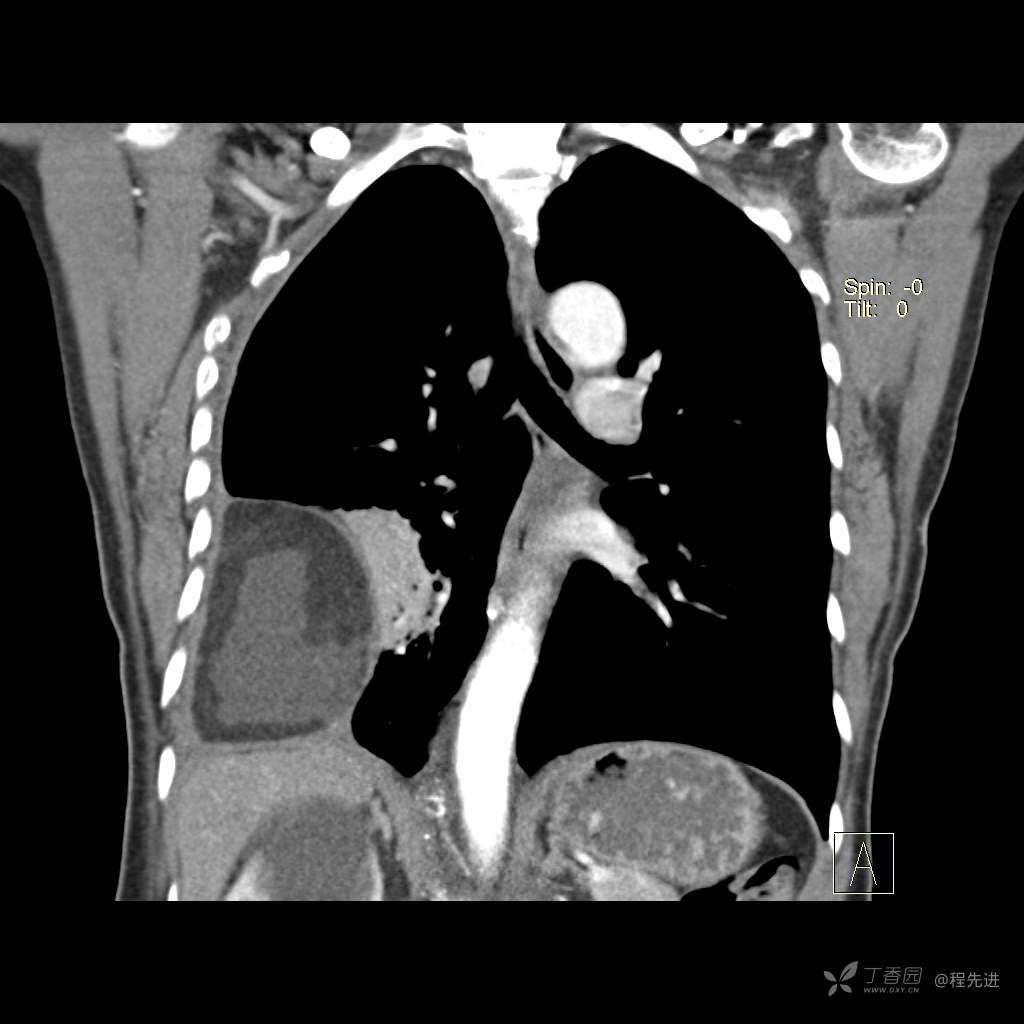

患者性别:女

患者年龄:51岁

简要病史:胸闷半年